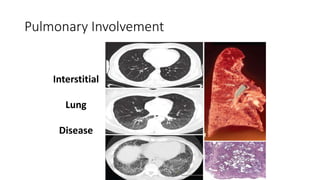

Pulmonary Involvement

Interstitial

Lung

Disease